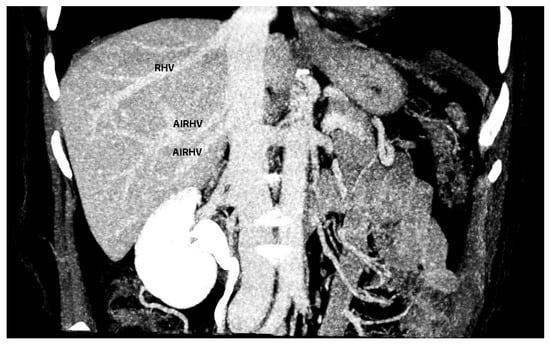

Significance of Liver Shape Variations in Ovarian Cancer Surgery

7. Macroscopic and Microscopic Anatomy of the Liver—One Entity